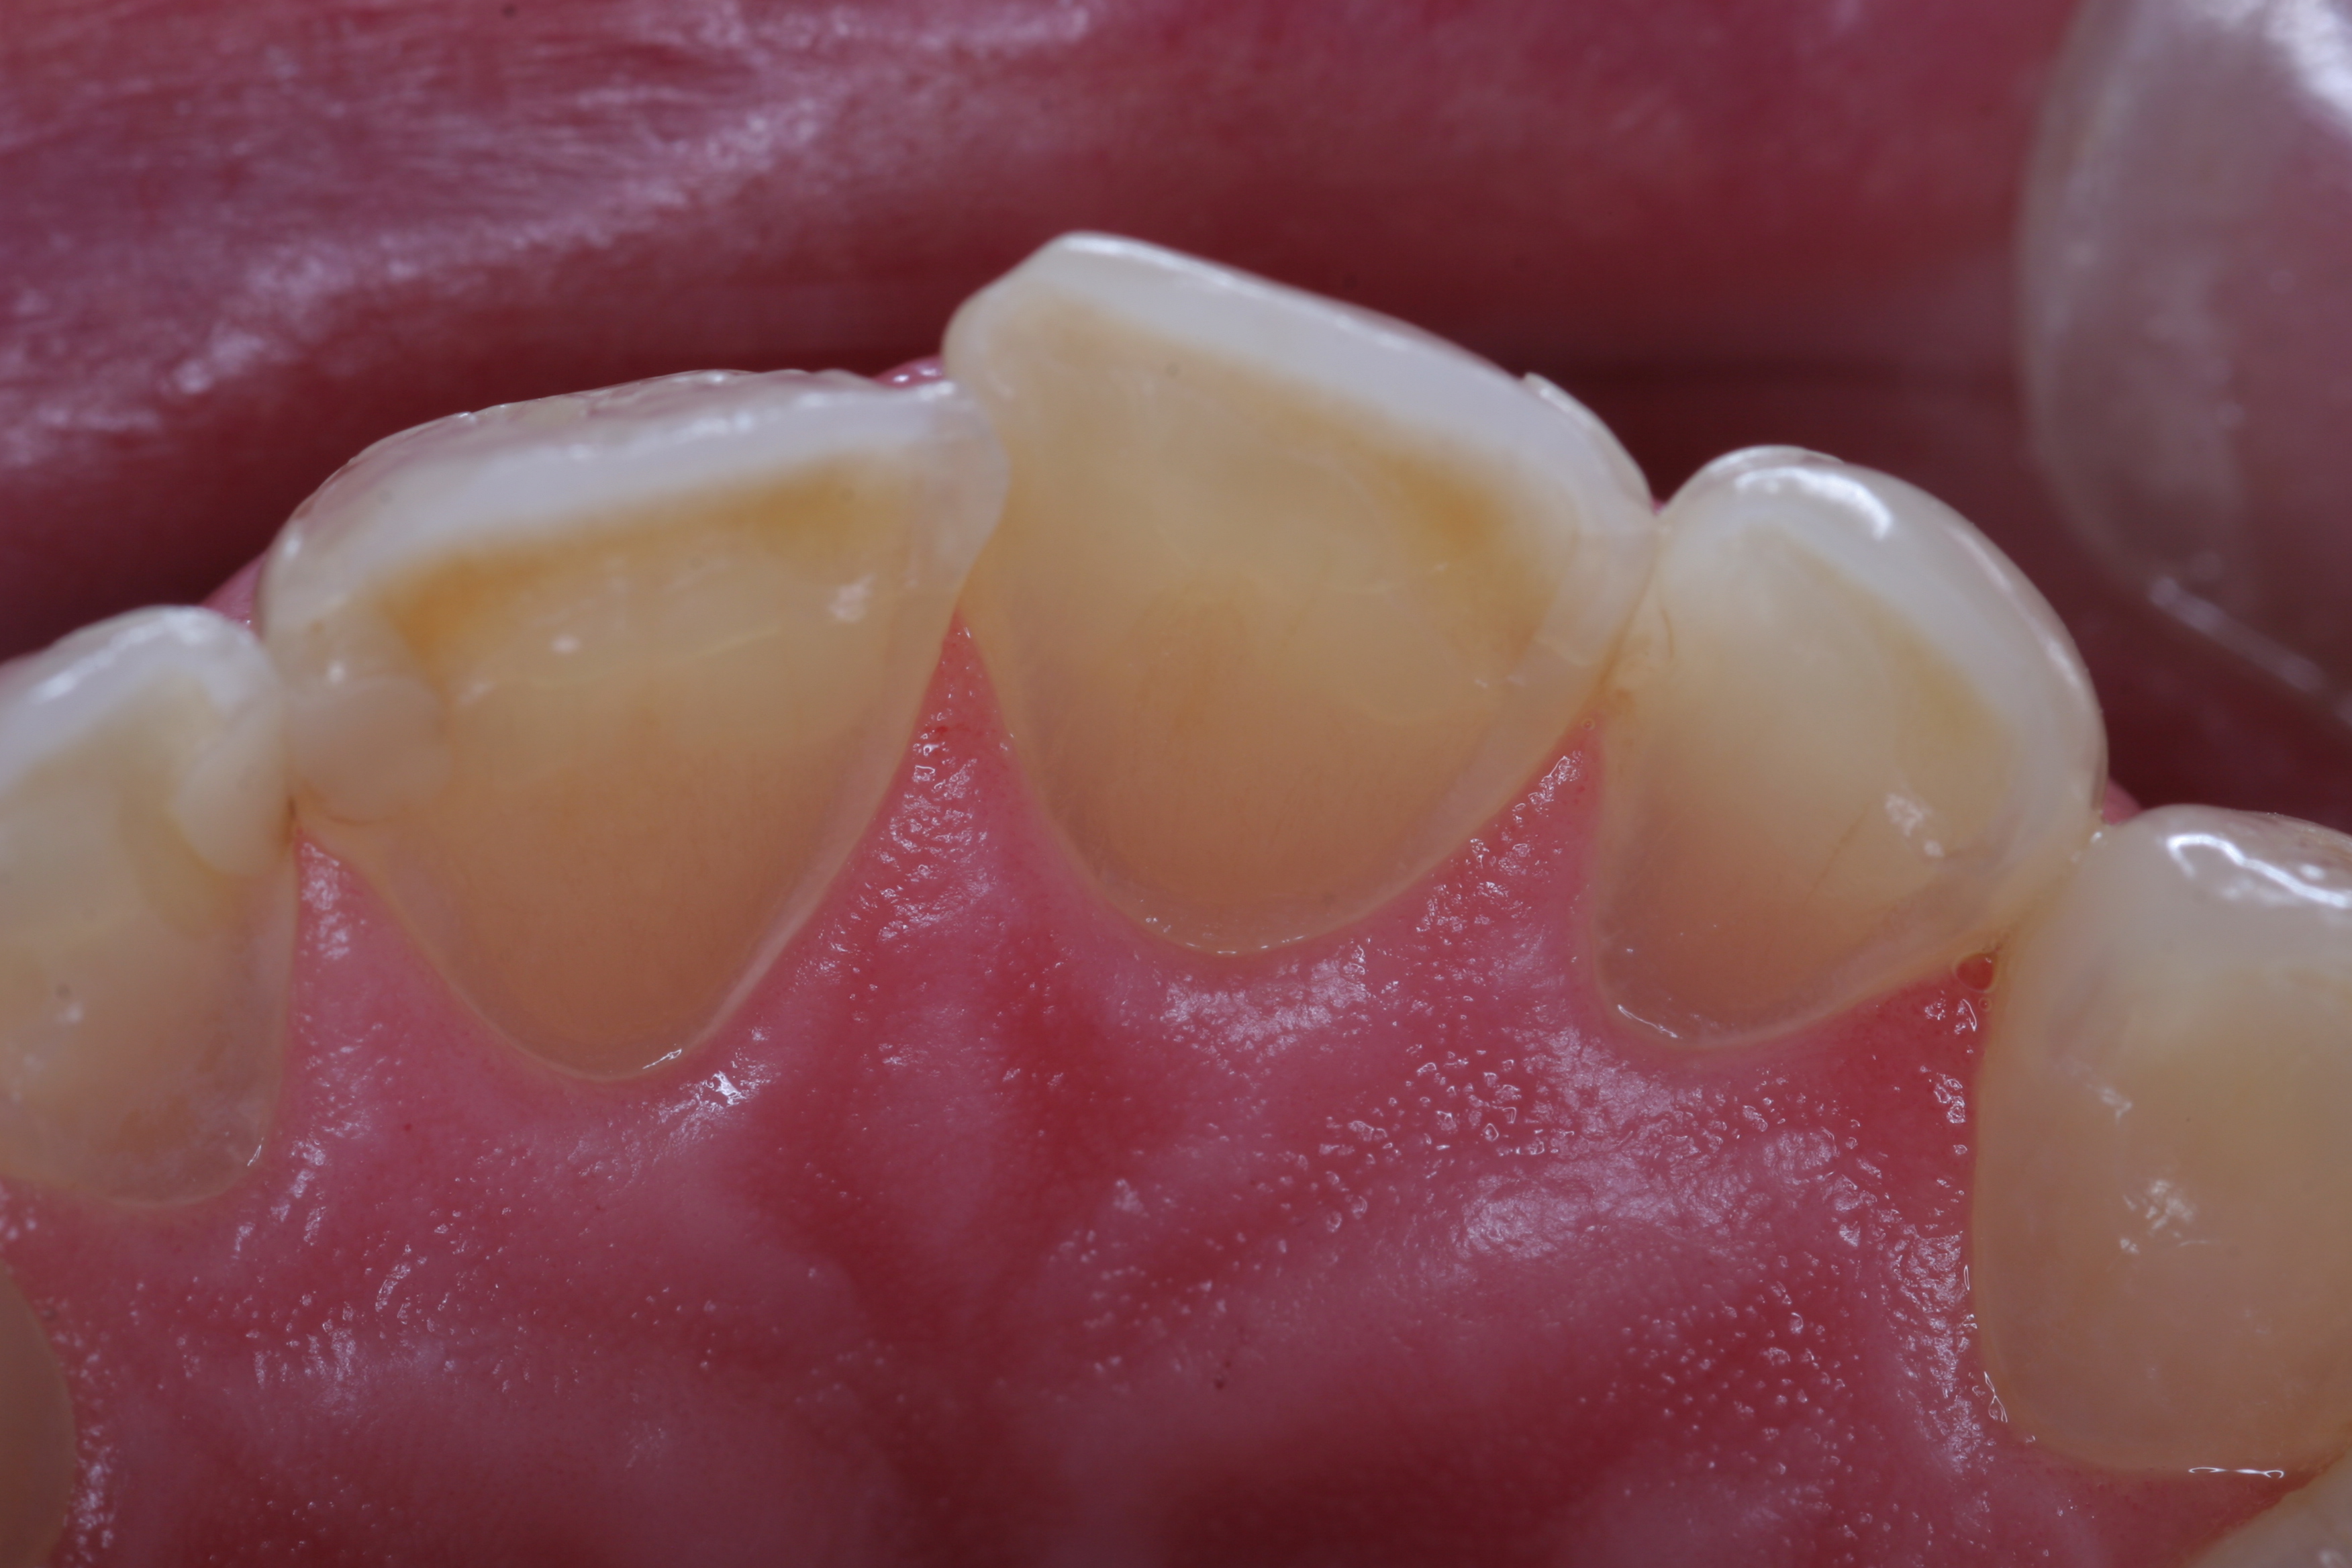

(5.) The anterior teeth must have sufficient lingual contour to allow immediate disclusion of the posterior teeth.

Figure 5

Abfraction was a term first described by John O. Grippo, DDS, in 1991. These cervical-type lesions result from concentrated stress transmitted through occlusal loading forces. With regard to lateral forces in the posterior region, loaded teeth showed a loss of enamel 10 times greater than unloaded teeth.8 Inadequate canine and protrusive guidance can also lead to excessive posterior tooth abrasion and advanced wear. The anterior teeth must have sufficient lingual contour to allow immediate disclusion of the posterior teeth (Figure 5). Separation of the posterior teeth neurologically shuts down the elevator muscles of mastication.9 This separation is critical to prevent excessive lateral forces on the posterior dentition. Posterior teeth are designed to accept axial loading forces only. Lateral force on posterior teeth is a concern, because bite forces can be nine times greater when the posterior teeth are in contact versus anterior disclusion and posterior separation.10